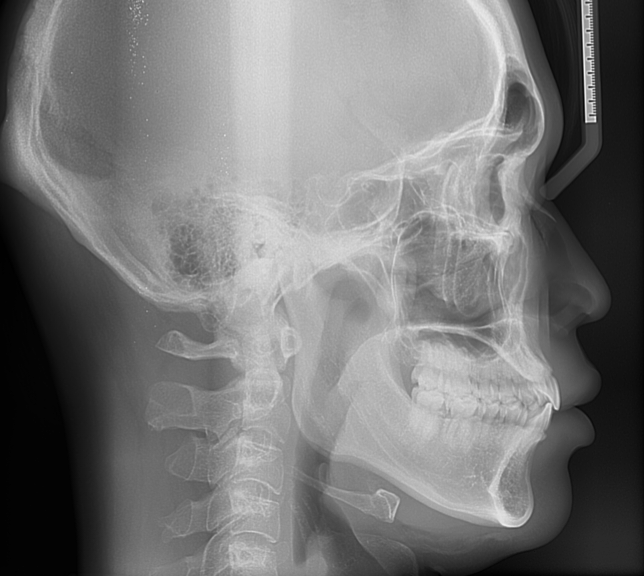

사진으로만 봤을 경우에는 입이 돌출된듯해 보입니다.

주걱턱은 보통 아래 치아가 위에 치아와 반대 교합을 이루고 있을 경우를 말하기 때문에 세팔로 사진상으로 봤을 경우에는 주걱턱이라고 하기 힘듭니다.

하지만 위의 치조골의 위치가 앞으로 나와있을 경우에는 그에 맞춰서 아래 치아와 턱의 위치가 결정되기 때문에 평균적인 형태보다는 앞에 위치할수 있어요.